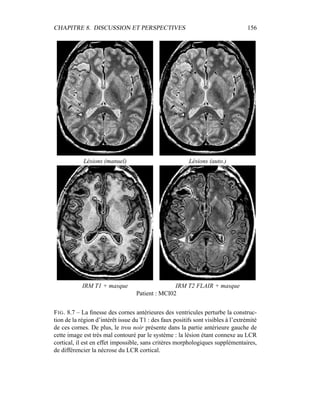

par contraintes spatiales.

Dans sa formulation la plus simple, le processus de segmentation prend un

ensemble multi-séquences à segmenter – les deux images T2 / densité de pro-

tons, auxquelles le masque binaire du cerveau a été appliqué – et fournit en sortie

3 labélisations : matière blanche, matière grise, LCR. Comme indiqué dans les